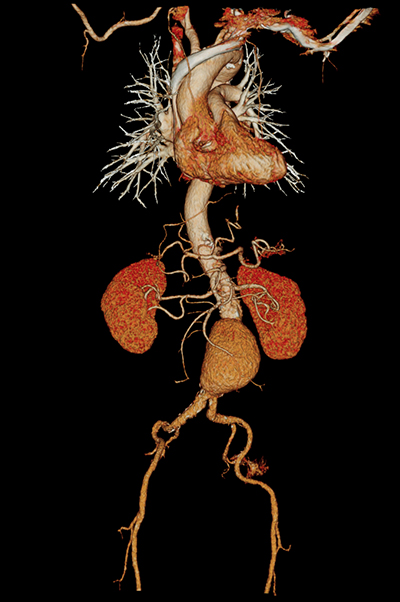

Передовые клинические решения Canon Medical гарантируют превосходную визуализацию сосудистой сети в исследованиях CTA, в то время как Iodine Mapping обеспечивает дополнительный уровень детализации в рамках

Вычитание СТА

Превосходная визуализация в CTA с истинным вычитанием кости и кальция

Йодное картирование

Четко определенное распределение йода с цветными картами кровотока